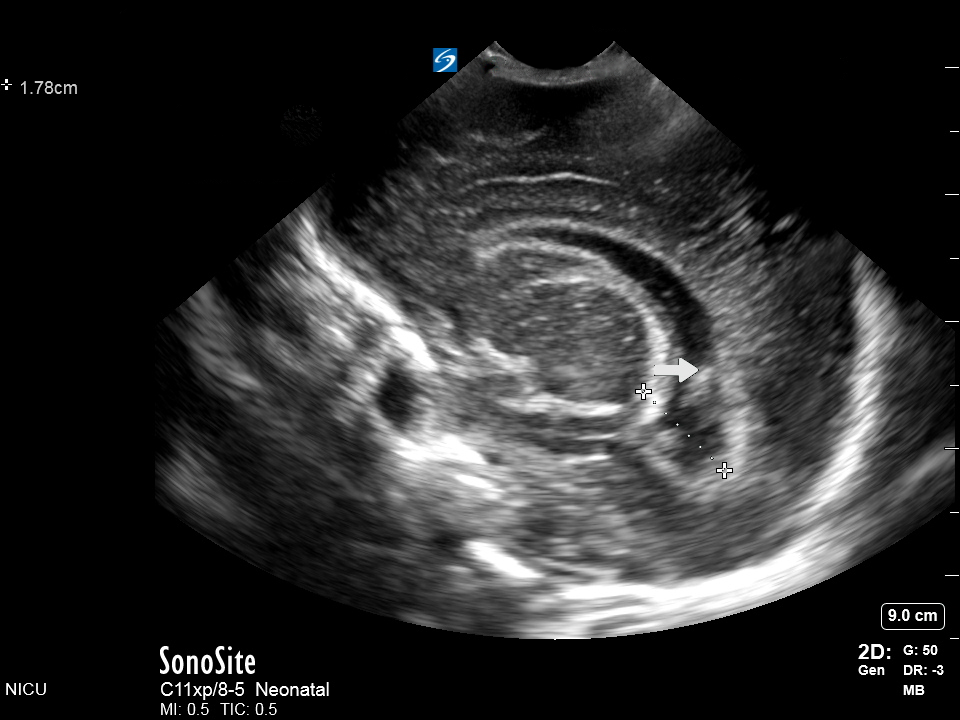

Neonatology Sagittal View Occipital Horn Clot 2 Image